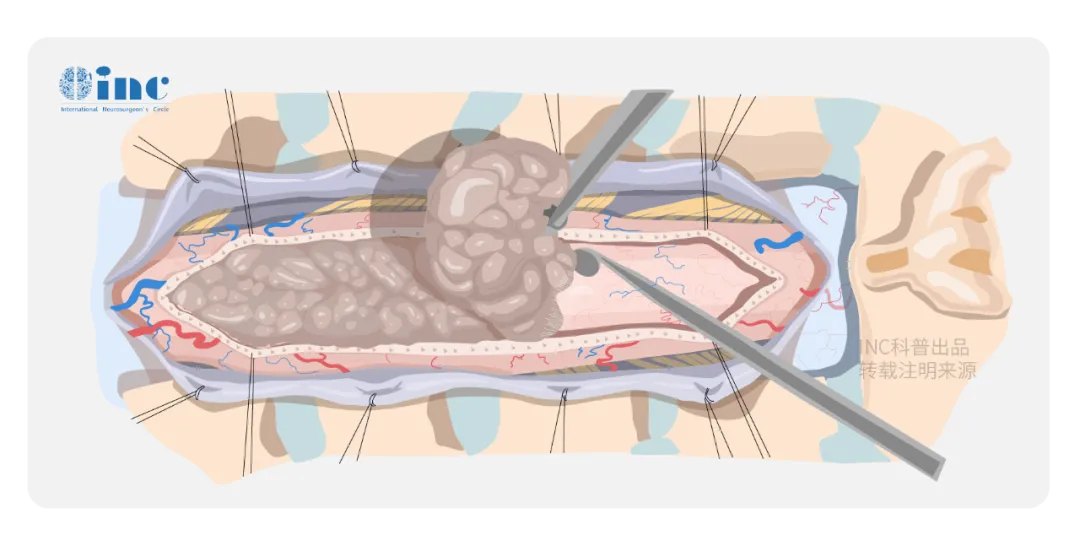

脊髓作为连接大脑与周围神经系统的主要通路,密布31个脊髓神经节和来自脑干的四条运动神经束。而如果肿瘤生长在脊髓内,位置处于外科手术的“禁区”:所在区域部位深、被脊骨包围、暴露困难,脊髓是很娇嫩的组织,稍受挤压或碰撞,即可造成长期性的障碍,下肢瘫痪、大小便失禁等。如果两侧的神经根如果出现破损,病人也可能出现瘫痪。手术后可能会瘫痪是根植在每一个罹患脊髓髓内肿瘤患者心中较深处的恐惧。

手术中怎么办才能避免对脊髓的损伤吗?

电生理监测可在诸多方面有助于神经外科医生的判断。每例脊髓肿瘤手术均应进行持续同步的术中感觉诱发电位(SEPs)和MEPs监测,并由专职的神经生理学家操作。一,使医生易于鉴别神经结构,特别是对于那些因肿瘤、外伤或以前的手术已使脊髓结构发生改变的病例;二,可指导手术切除病变的程度和范围,以便保护神经功能;三,可有助于确定病变在传导功能受损神经上的解剖定位。

“根据我的手术经验,在保留脑干和脊髓中运动感觉神经功能的前提下,手术是可行的。手术中需有电生理监测。”